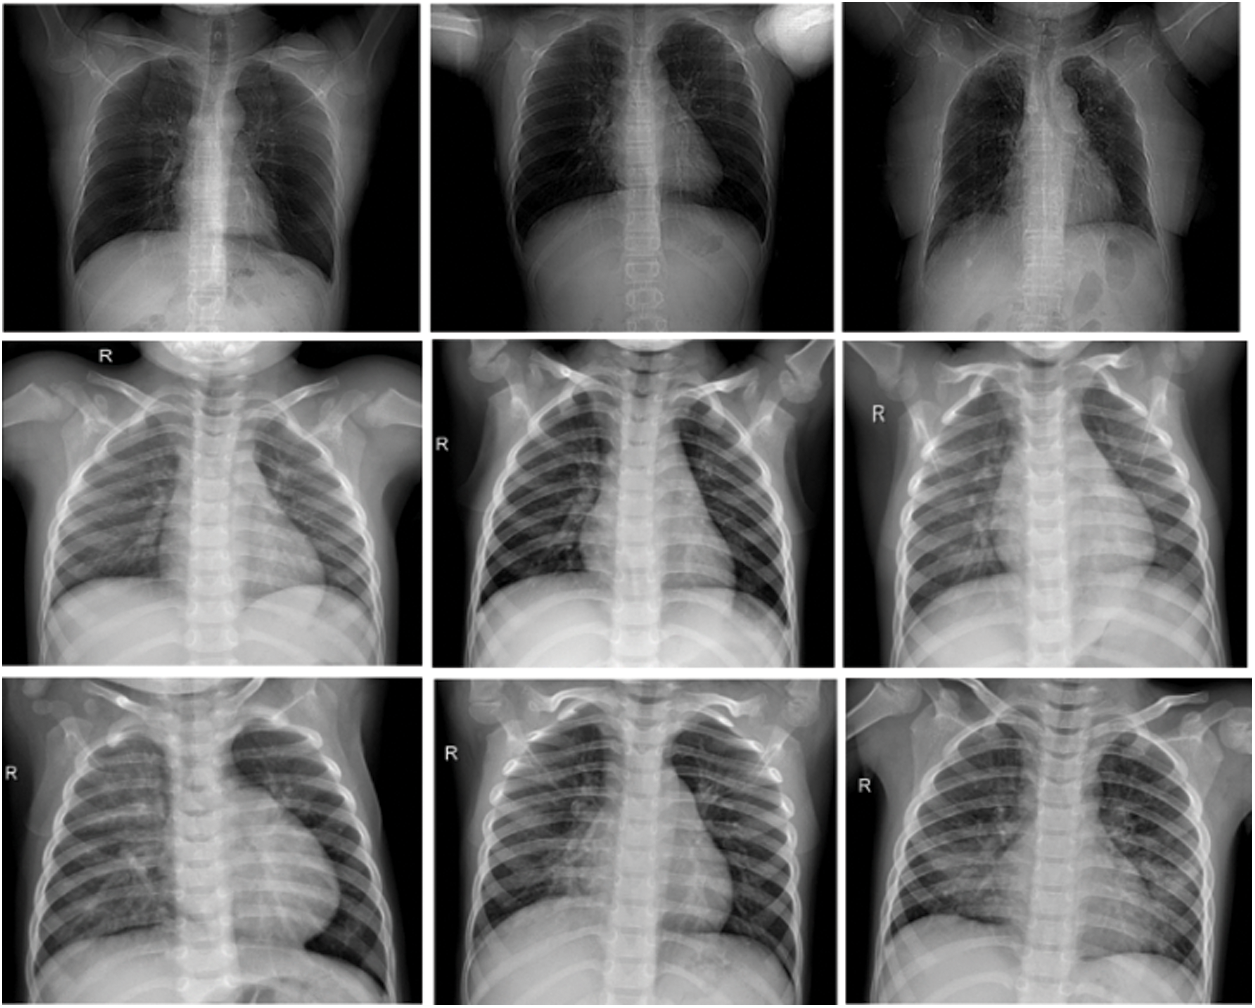

A dataset is a necessary and initial step in training machine learning models. The authors have chosen the COVID-19 dataset using the open-source Kaggle repository because it is a dataset that has been verified by different experts. Samples of chest X-ray images based on the specified dataset are as shown in Fig. 4. The original dataset consists of 2800 images. The first row contains the images of human chests infected by COVID-19, the second row contains Normal, and the third one contains X-ray images of patients with Pneumonia. However, augmentation is performed on the COVID-19 category by the authors to equalise the images and avoid the data difference between categories and the details of the augmentation. However, as shown in Fig. 4, the dataset contains a total of three categories of Normal, COVID-19, and Pneumonia with 1000 chest X-ray images of each category. Furthermore, the authors have divided the whole dataset into evaluation sets (80%) and training dataset (20%) as shown in Fig. 5.

Figure 4: Samples images from used COVID-19 dataset